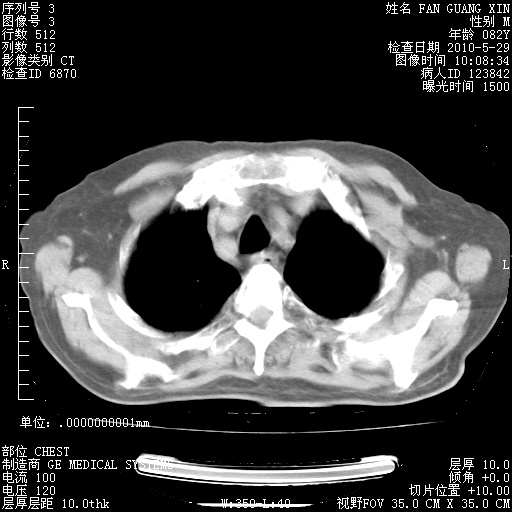

再治疗10天后的肺部CT

再治疗10天后的肺部CT 纵膈窗

阅读此次胸部CT,肺间质渗出性改变较入院时有吸收。目前从体温、白细胞、中性分叶明显增高,肯定存在细菌感染(发生医院感染哦,若无消化道及泌尿系统等感染的依据,肺部感染可能大)。若你院头孢哌酮舒巴坦钠耐药率较高,同意你的方案,若48小时体温仍高,可考虑使用碳青霉稀类抗菌药物,同时可予超声雾化、注意滴数时加大液体量。白蛋白33.30g/L较低哦,需加强营养等支持治疗。